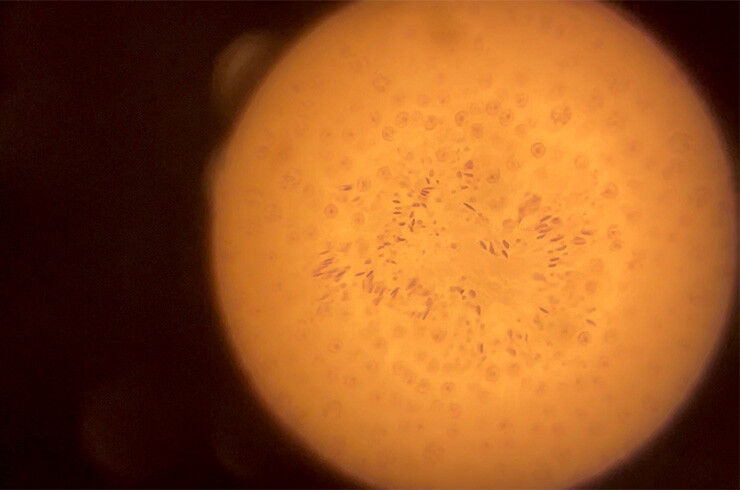

Peters’ team investigates how this packaging influences which genes are active in eggs, sperm, and early embryos. Using mouse models, his team removes specific chromatin components from developing gametes and observes how this affects fertilization and embryogenesis. These experiments revealed that the chromatin "flavors"-- open or closed - inherited from each parent are essential for proper genome activation after fertilization.

The researchers discovered that in eggs, a chromatin-based mechanism safeguards regulatory regions from methylation. When this mechanism fails, methylation spreads to areas that should remain active. Although the eggs appear normal, the embryos cannot develop after fertilization or implant in the mother’s womb.

In mice, removing the enzymes responsible for DNA methylation in eggs rescued defects in embryonic development, the researchers found. The findings, published in Developmental Cell in September, suggest that chromatin states inherited from the egg determine which genes the embryo can activate after fertilization.